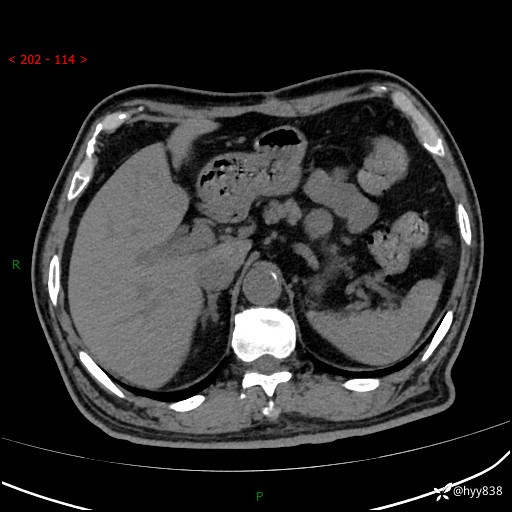

69岁/男,四肢无力3月余。胰腺囊实性占位,渐进性强化---结果公布~

【患者信息】:69岁/男

【主诉】:四肢无力3月余。

【现病史及既往史】:患者3月前无明显诱因出现四肢乏力,伴有口干、多饮、多尿等症状,无畏寒、发热、恶心、腹痛、腹泻等其他症状,于2024-06-13来我院住院治疗,完善相关辅助检查后,考虑“2型糖尿病”,予以降糖(阿卡波糖片 50mg po tid、德谷门冬双胰岛素注射液 8iu 早餐前 皮下注射)等治疗,口干、多饮、多尿较前缓解,血糖控制可;现仍存在四肢乏力,于2024-08-28来我院门诊就诊,查血钾2.88 mmol/L ,现以“低钾血症”收入我科。 本次起病以来,患者精神、饮食、睡眠良好,二便正常,近3月余体重下降约5kg。

【检查】:胰腺CT平扫+增强